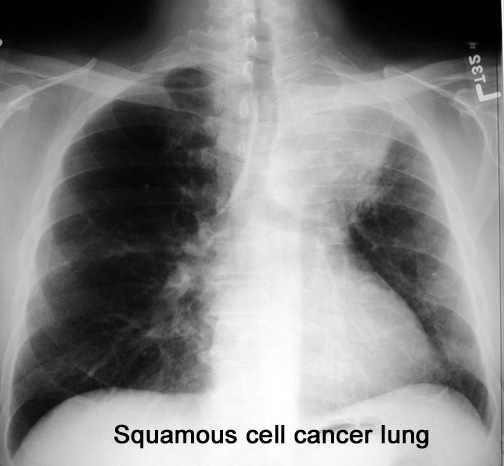

Case 25 Labeled Image What are the features of cavitating lung cancer?